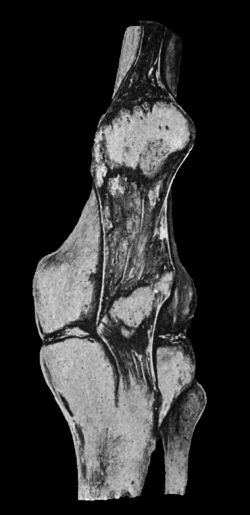

| 61. | Fracture through Narrow Part of Neck of Femur on Section | 131 |

| 62. | Impacted Fracture through Narrow Part of Neck of Femur | 132 |